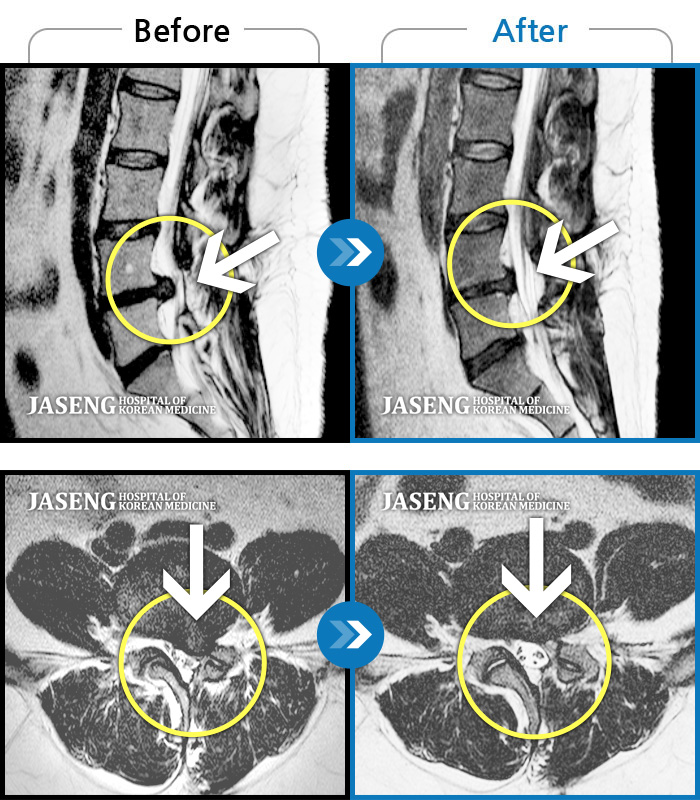

허리디스크

인천 · 조남훈 원장

좌측 허벅지와 종아리가 찌릿하고 묵직한 통증이 있어요.

촬영시기

2025.03.18 ~ 2025.07.22

2025.08.01